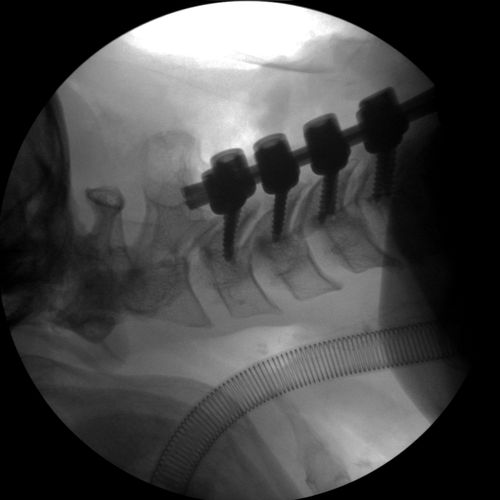

Cervical Spine Fixation

Dorsal Lumbar Fixation